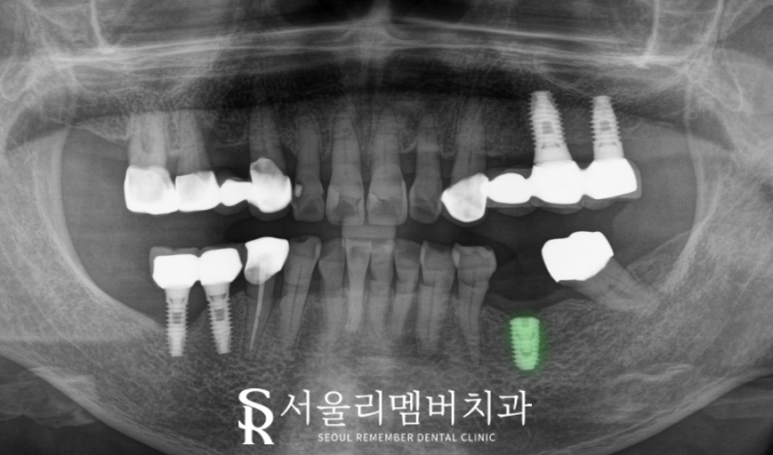

오늘 신림역 치과 의 케이스는

하악 좌측 제1대구치의 결손으로 인하여

그 뒤의 제2대구치가 앞으로 쓰러져가는 상황이라

치료 기간을 단축시키는 것이

무엇보다 중요했습니다.

그렇지 않으면

뒷니가 점점 더 많이 기울어져서

공간이 좁아지다 보니

보철을 올릴 수 없게

될 수도 있기 때문이죠.

그래서 빠른 회복 치료 기간 단축을 위해

오스템 BA를 식립하였으며

2개월이 좀 넘었음에도

이렇게 뼈와 단단히 붙은 것을

확인할 수 있었습니다.

보통 3~4개월 정도 소요되는데

특수 표면 처리로 인해

이보다 짧은 기간에 골유착이 이루어져

바로 상부에 보철을 올려드릴 수 있었습니다.

그 덕분에 신림역 치과 에서 걱정하던

뒤어금니의 쓰러짐도 빠르게

예방해 드릴 수 있었죠.